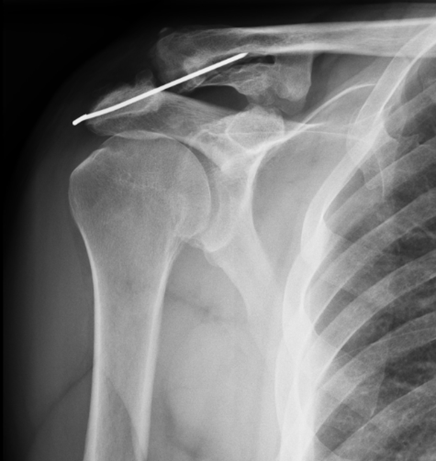

A 53-year-old patient was diagnosed with a grade III dislocation of the right acromioclavicular joint. The dislocated joint was fixated using 2 Kirschner wires. Two years later, during surgical reinsertion of a torn long head tendon of the bicep muscle, one of the two Kirschner wires was removed. Four years following the first operation, an x-ray of the joint showed a broken Kirschner wire and the migration of one element to the right suprascapular soft tissue. The remaining fragments of the wire were surgically removed.